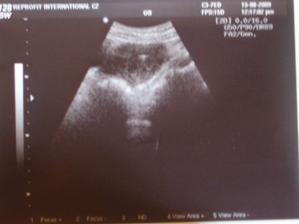

Únor 2009.. 5. pokus - ET 2 embrya - PK, hatchující blastocysty.. Podařilo se!!! Zase těhotná, potvrzena jedna krásná naděje, podle UTZ celá tatínek. Huráá! .............

Srpen 2009.. 7. pokus - ET 2 embrya - PK, blastocysty.. Transfer byl v den, kdy naše jméno pro holčičku mělo svátek. O šest dní později jsem testla 🙂 .. Od toho dne jsem začala špinit a večer 18. den po ET i krvácet. Dopoledne to přestalo, ale až UTZ nám poví, jak to je..

Je to v .. v 7tt zamlklé.. ........................